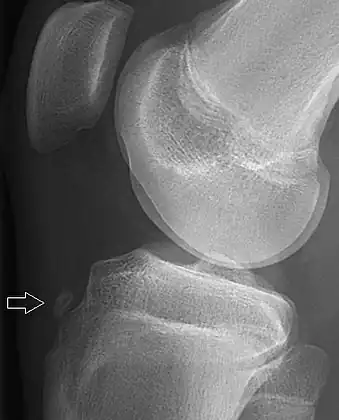

- Knee showing tibial tuberosity avulsion fracture (and proximal tibial fracture)

- X-ray of a 15-year-old male, showing an older avulsion fracture of the tibial tuberosity.